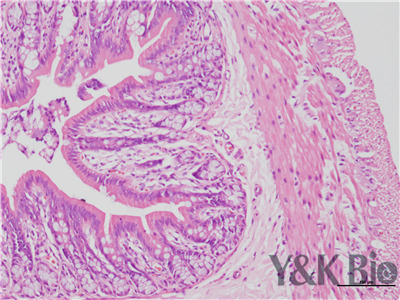

HE病理片子全景扫描是将物质化的玻片标本快速数字化的过程,能高效、高清晰、全信息的图像采集,是真正脱离显微镜的阅片方式。还能够长期保存,可满足临床、科研、教学等多种用途。陕西依科生物可根据客户需要,提供个性化服务,可满足不同应用的软、硬件zy服务解决方案。该公司的HE病理片子全景扫描,可适应不同玻璃切片,确保凸凹不平的切片图像不会失焦模糊.